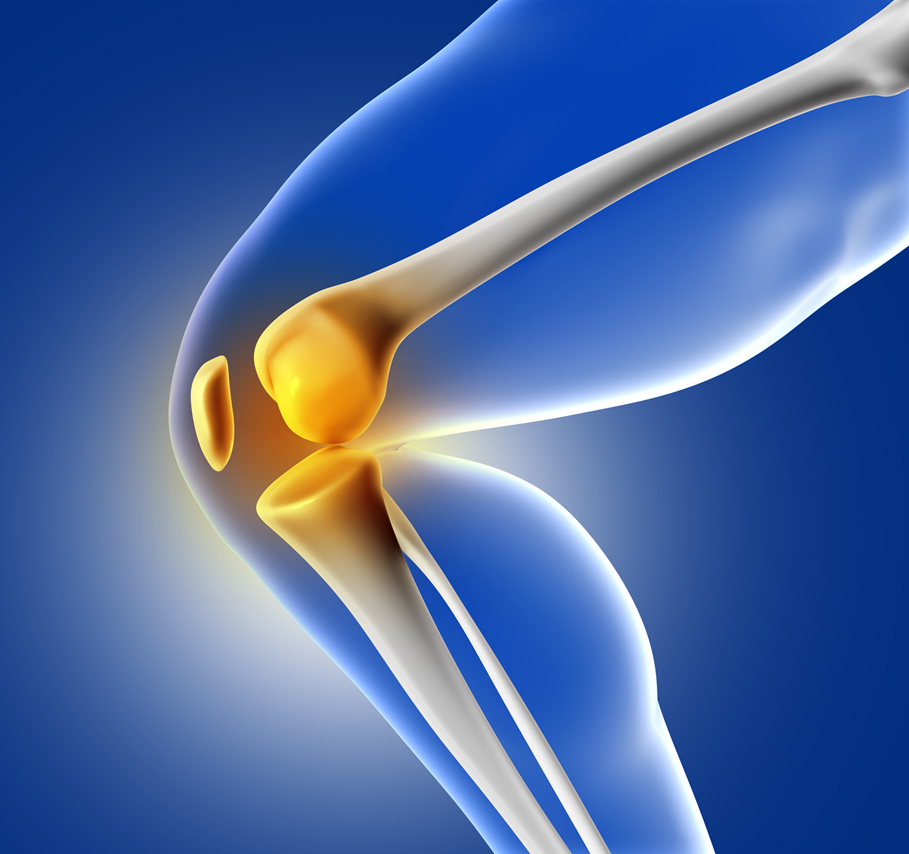

Primary & revision knee replacement surgery

A surgical procedure designed to replace damaged knee joint surfaces and relieve long-standing pain caused by arthritis, injury, or joint degeneration. By restoring smooth movement and proper alignment, knee replacement helps patients regain mobility and return to daily activities comfortably. Revision knee replacement addresses issues related to a previous implant such as wear, loosening, or instability. Using advanced techniques, the joint is reconstructed to improve function, stability, and long-term performance.

Primary Knee Replacement

Primary knee replacement is a highly successful procedure designed to relieve chronic pain caused by arthritis, cartilage loss, deformity, or longstanding joint damage. By replacing the worn-out surfaces of the knee with durable implants, the surgery restores smooth movement and eliminates friction within the joint. Most patients experience significant improvement in mobility, reduced stiffness, and a renewed ability to perform daily tasks comfortably.

The surgery uses advanced techniques and precise alignment methods to ensure the implant functions as naturally as possible. With modern materials and design, knee implants can last many years, allowing patients to enjoy an active lifestyle without the limitations imposed by chronic knee pain. Early mobilisation after surgery also plays a key role in improving long-term results.

Revision knee replacement

Revision knee replacement is a highly successful procedure designed to relieve chronic pain caused by arthritis, cartilage loss, deformity, or longstanding joint damage. By replacing the worn-out surfaces of the knee with durable implants, the surgery restores smooth movement and eliminates friction within the joint. Most patients experience significant improvement in mobility, reduced stiffness, and a renewed ability to perform daily tasks comfortably.

The surgery uses advanced techniques and precise alignment methods to ensure the implant functions as naturally as possible. With modern materials and design, knee implants can last many years, allowing patients to enjoy an active lifestyle without the limitations imposed by chronic knee pain. Early mobilisation after surgery also plays a key role in improving long-term results.